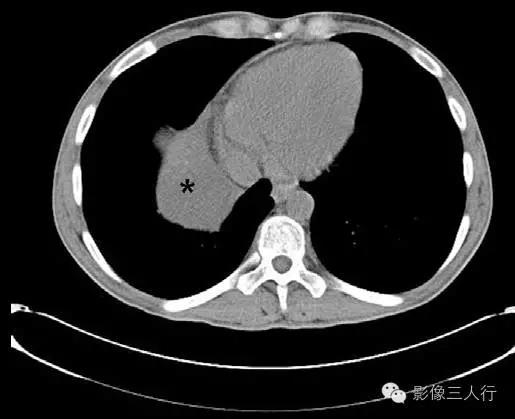

影像表现心包囊肿是一种先天性病变,是心包在早期发育期形成断口的部分所致。心包囊肿可发生于纵隔内的任何部位,但最常见于心膈角。在CT上,典型的心包囊肿无分隔,薄壁甚至不能发现(图1)。对比剂增强后不强化(图2和图3)。心包囊肿通常为水密度,密度可较高,但罕见。在这些病例中,MRI常有助于确定病变的液体性质。囊肿通常在T1加权成像上呈低到中等 信号强度,但在囊肿内含蛋白物质的病例的T1加权成像可呈高信号。囊肿在T2加权成像上呈均匀高信号强度。

图1:胸部CT平扫显示液体密度肿块(*)起于纵隔右侧。未见壁存在,肿块与心包相连。表现为典型心包囊肿